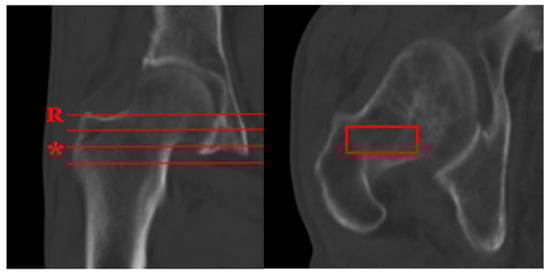

- Planar selection: Identify the coronal slice demonstrating the maximal cross-sectional area of intertrochanteric cancellous bone, which typically coincides with the central mechanical axis of the proximal femur.

- ROI placement: Position a rectangular ROI to fully encompass this cancellous bone area.

- Cortical exclusion: Carefully adjust the ROI to exclude the cortical bone boundaries.

- Data recording: Record the mean CT attenuation value (in Hounsfield Units) provided by the imaging software.